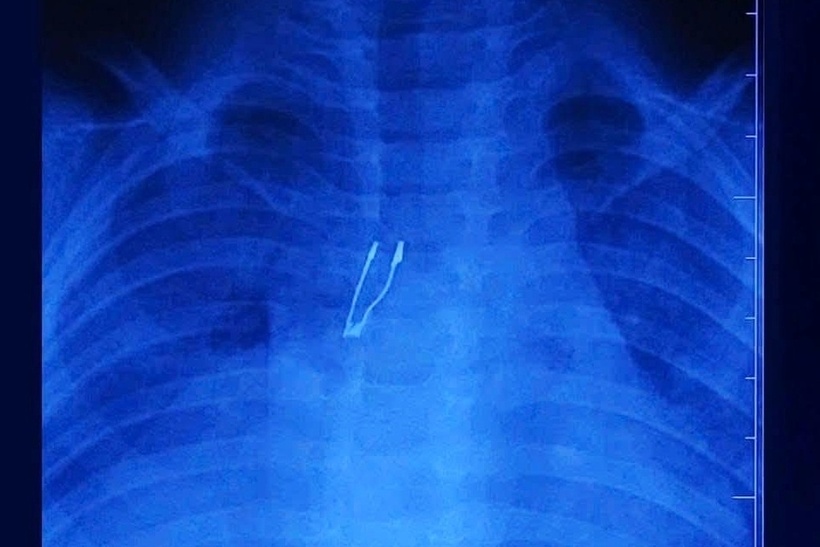

Tại Bệnh viện Nhi đồng 1, kết quả chụp chiếu hình ảnh cho thấy dị vật nằm ở phế quản gốc phải, kèm theo dấu hiệu xẹp phổi phải và tràn khí trung thất - những biến chứng báo hiệu tình trạng phức tạp.

Dị vật nghi ngờ là một bóng đèn LED, nằm sâu trong phế quản gốc phải. Ảnh: Pháp luật TP.HCM